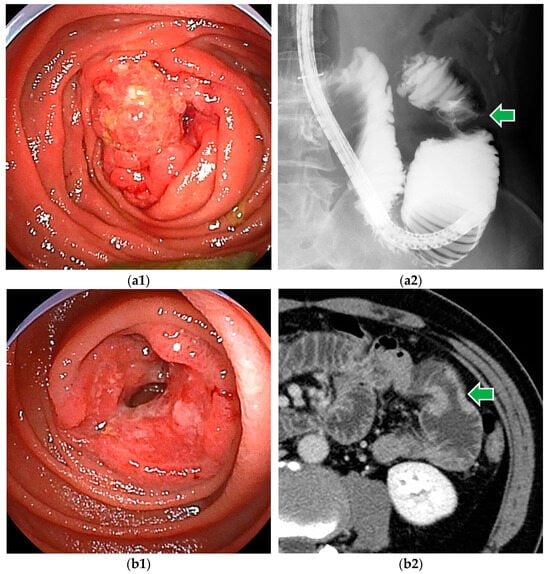

Figure 1.

Small bowel adenocarcinomas, which are often advanced at the time of diagnosis, and endoscopic findings often include ulceration and stenosis. (a1,a2) DBE revealed adenocarcinoma in the proximal jejunum. Endoscopic enteroclysis showed the stenosis as an apple core sign. (b1,b2) DBE revealed adenocarcinoma with ulceration. CT showed mild stenosis.

BAE, or push enteroscopy, can reach the lesion (Figure 1), take a biopsy for histopathologic diagnosis, and mark it by tattooing for surgical treatment. Endoscopic findings of small bowel adenocarcinoma often include ulceration and stenosis. Type 2 (54.2%) was the most common among the macroscopic types, followed by Type 3 (18.2%) [5].